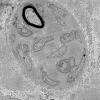

PERIPHERAL NEUROPATHY

1 NORMAL NERVE ANATOMY